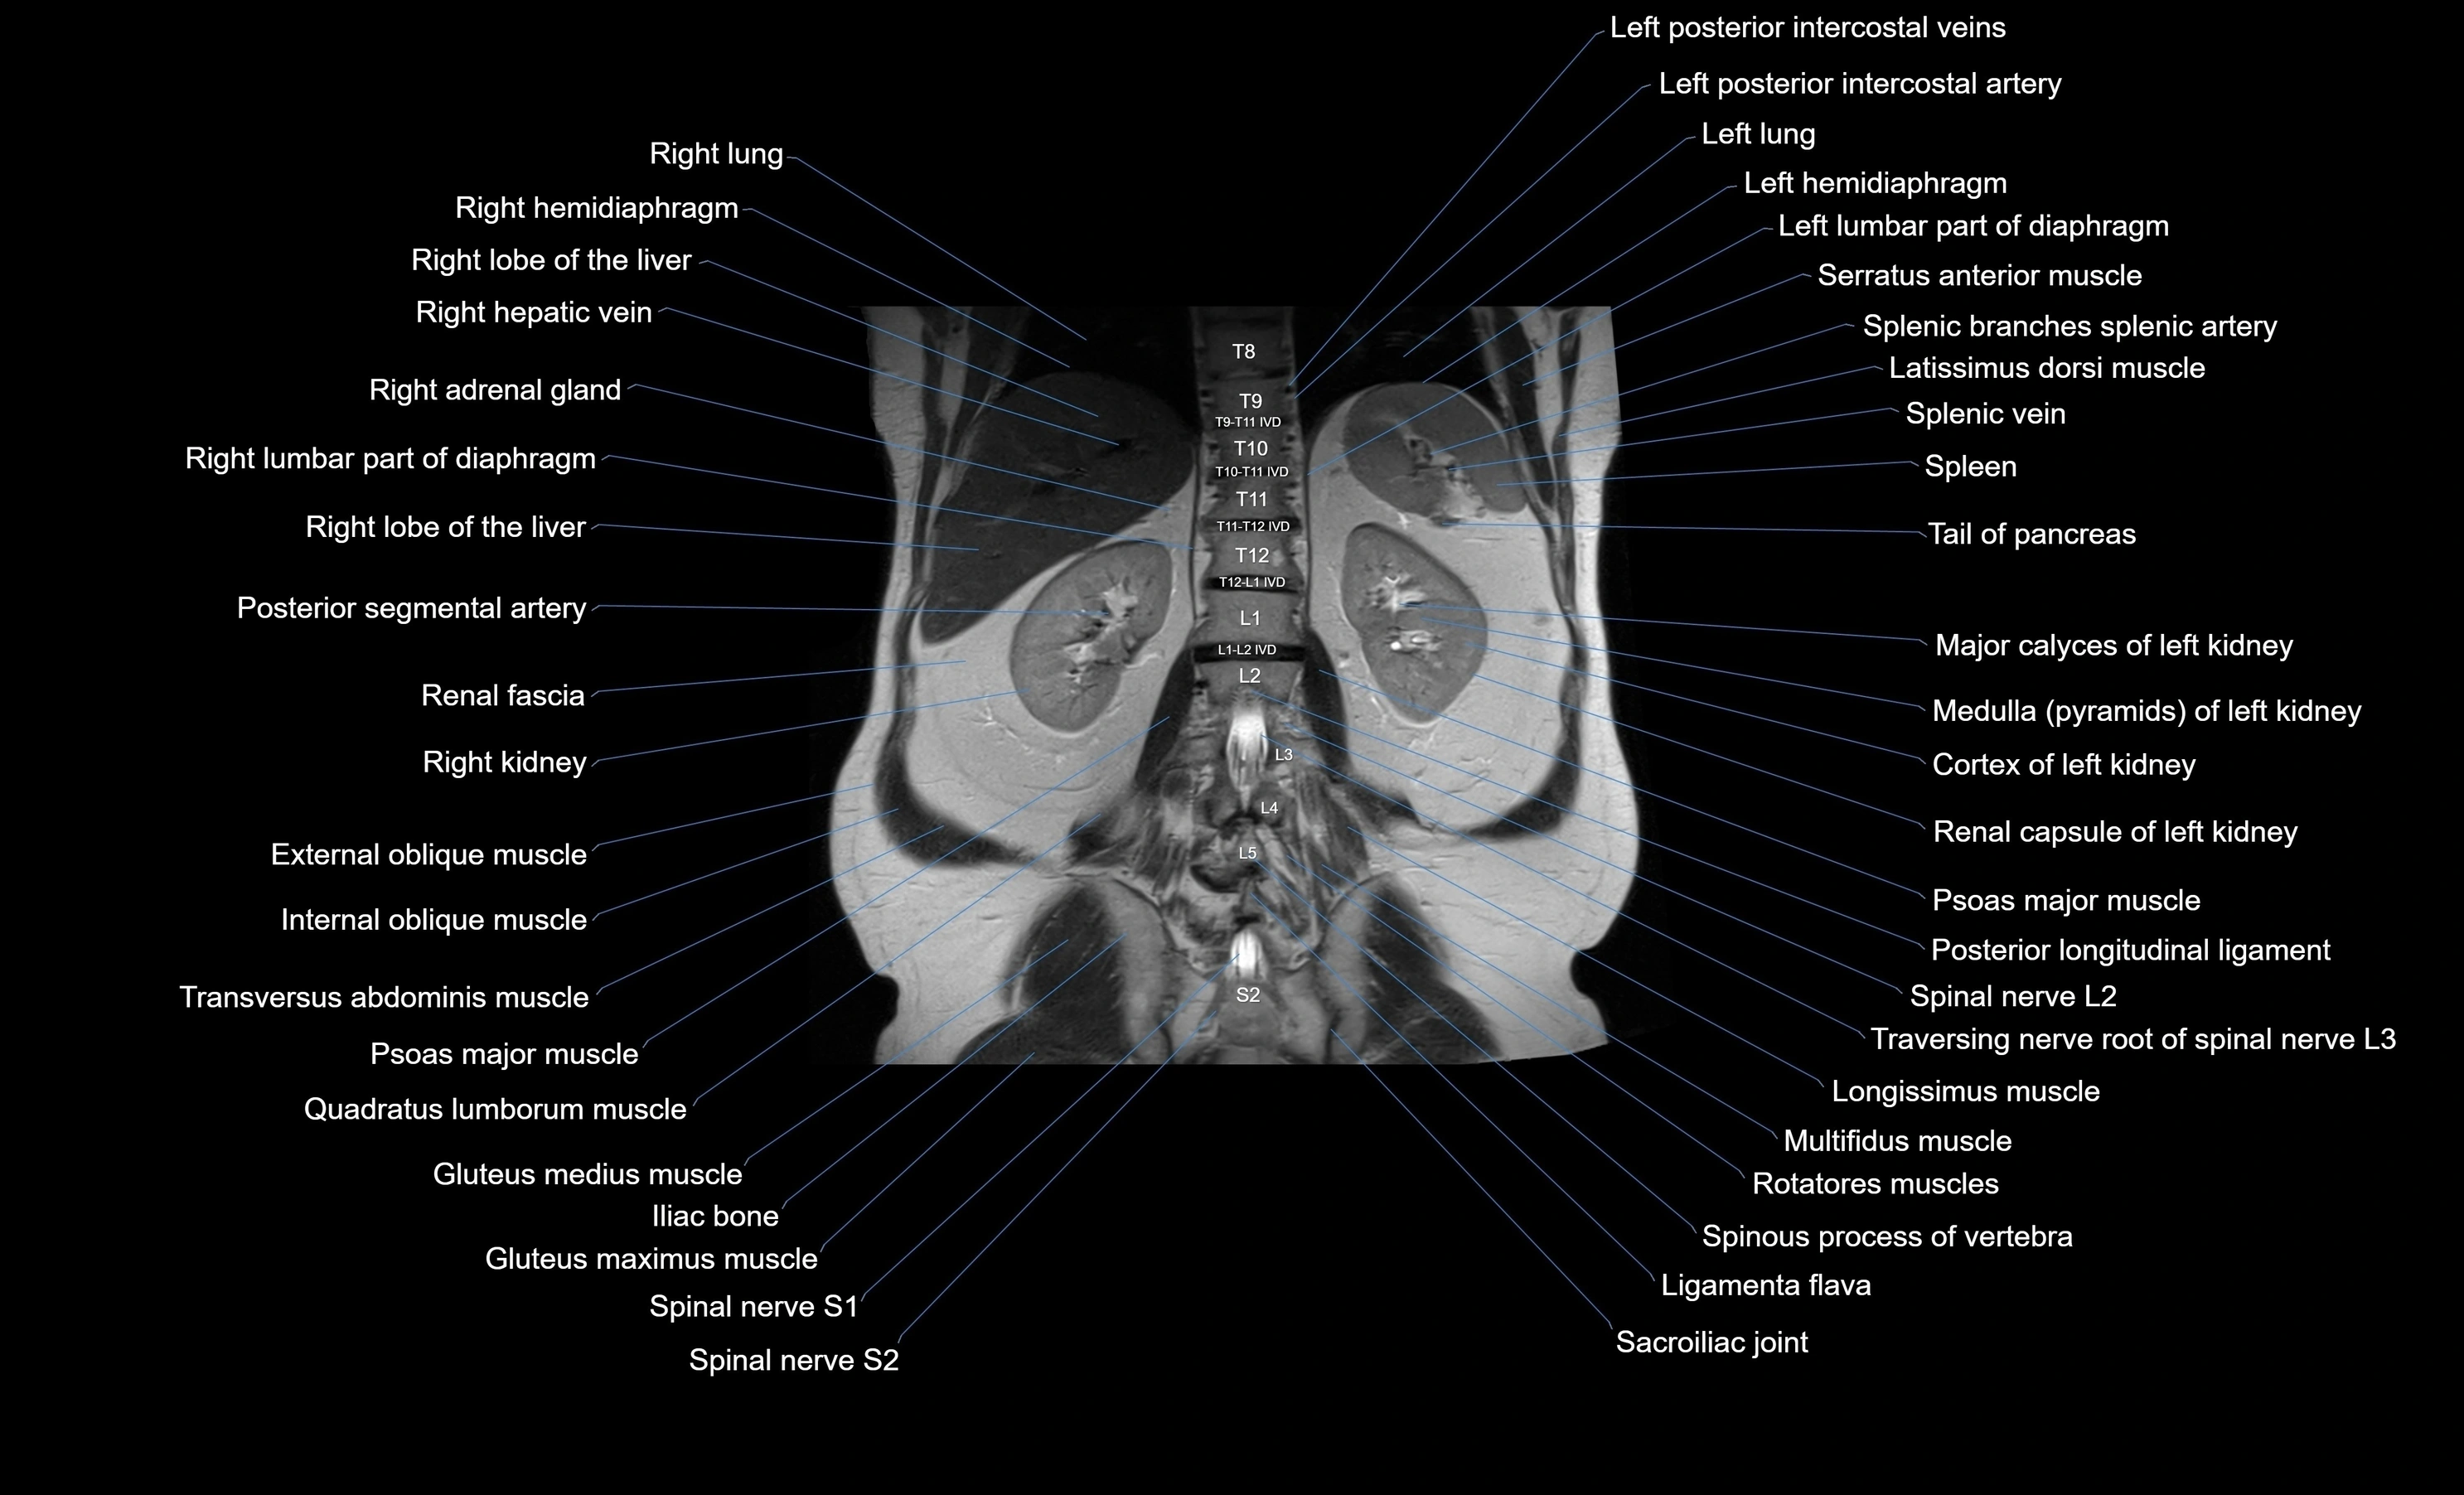

- Left kidney

- Right kidney

- Psoas major muscle

- Quadratus lumborum muscle

- Left hemidiaphragm

- Left lumbar part of diaphragm

- Lateral aortic lymph nodes

- Spinal nerve L2

- Spinal nerve L3

- Spinal nerve S1

- Spinal nerve S2

- Ligamenta flava (Ligamentum flavum)

- Rotatores lumborum muscles